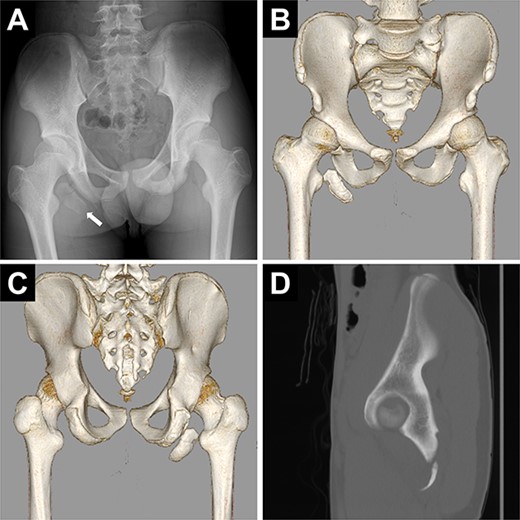

Postoperative images of the pelvis. (A) Plain radiograph. (B) Computed tomography scan.